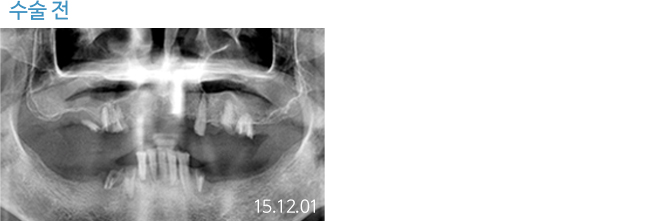

한 번 잘 심으면 10년 뒤에도 끄떡없는

더와이즈 임플란트

첨단 장비를 이용한 정확한 진단, 안정성이 입증된 정품 재료 사용,

노하우가 풍부한 숙련된 의료진의 시술 등이 임플란트 수명을 결정합니다.

※ 실제 본원에서 치료 받은 환자의 동의를 얻어 게재했습니다.

개인의 특성에 따라 부작용이 발생할 수 있으므로 담당의와 충분히 상의하시길 바랍니다.

THEWISE 치료별 전후사진